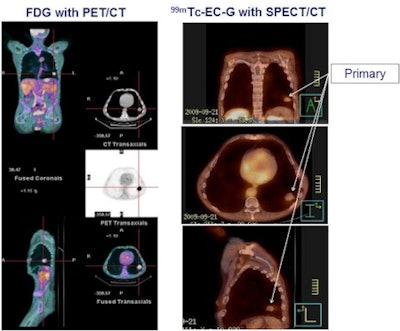

| Phase II result: Tc-99m ECG (right) is at least equivalent to FDG (left) in detecting primary NSCLC tumors (100% concordance). Image courtesy of medicalphysicsweb. |

Independent expert readers at a core lab assessed the images for location, size, and confidence that the detected lesions were cancer. For primary lesions, results showed 100% concordance between ECG and FDG on all three parameters, independent of the SPECT device used. In 17 patients with metastatic lesions, 90% agreement was seen for location, size, and confidence that detected lesions were metastases. No adverse drug-related events were reported.